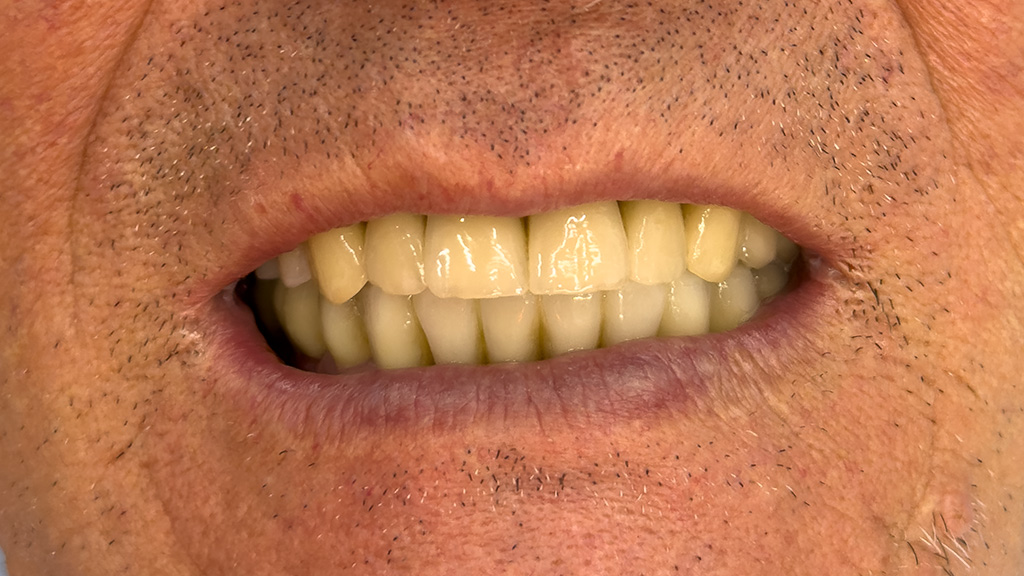

Paziente maschio 67 anni

Estrazione 9 elementi residui ed inserimento 10 impianti (6 SUP + 4 INF) a carico immediato provvisorio per ripristinare entrambe le arcate.

A distanza di 4 mesi verranno sostituite le Toronto Bridge provvisorie con le definitive.